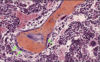

Fibrocartilage